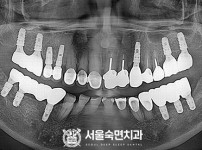

임플란트-전후사진3